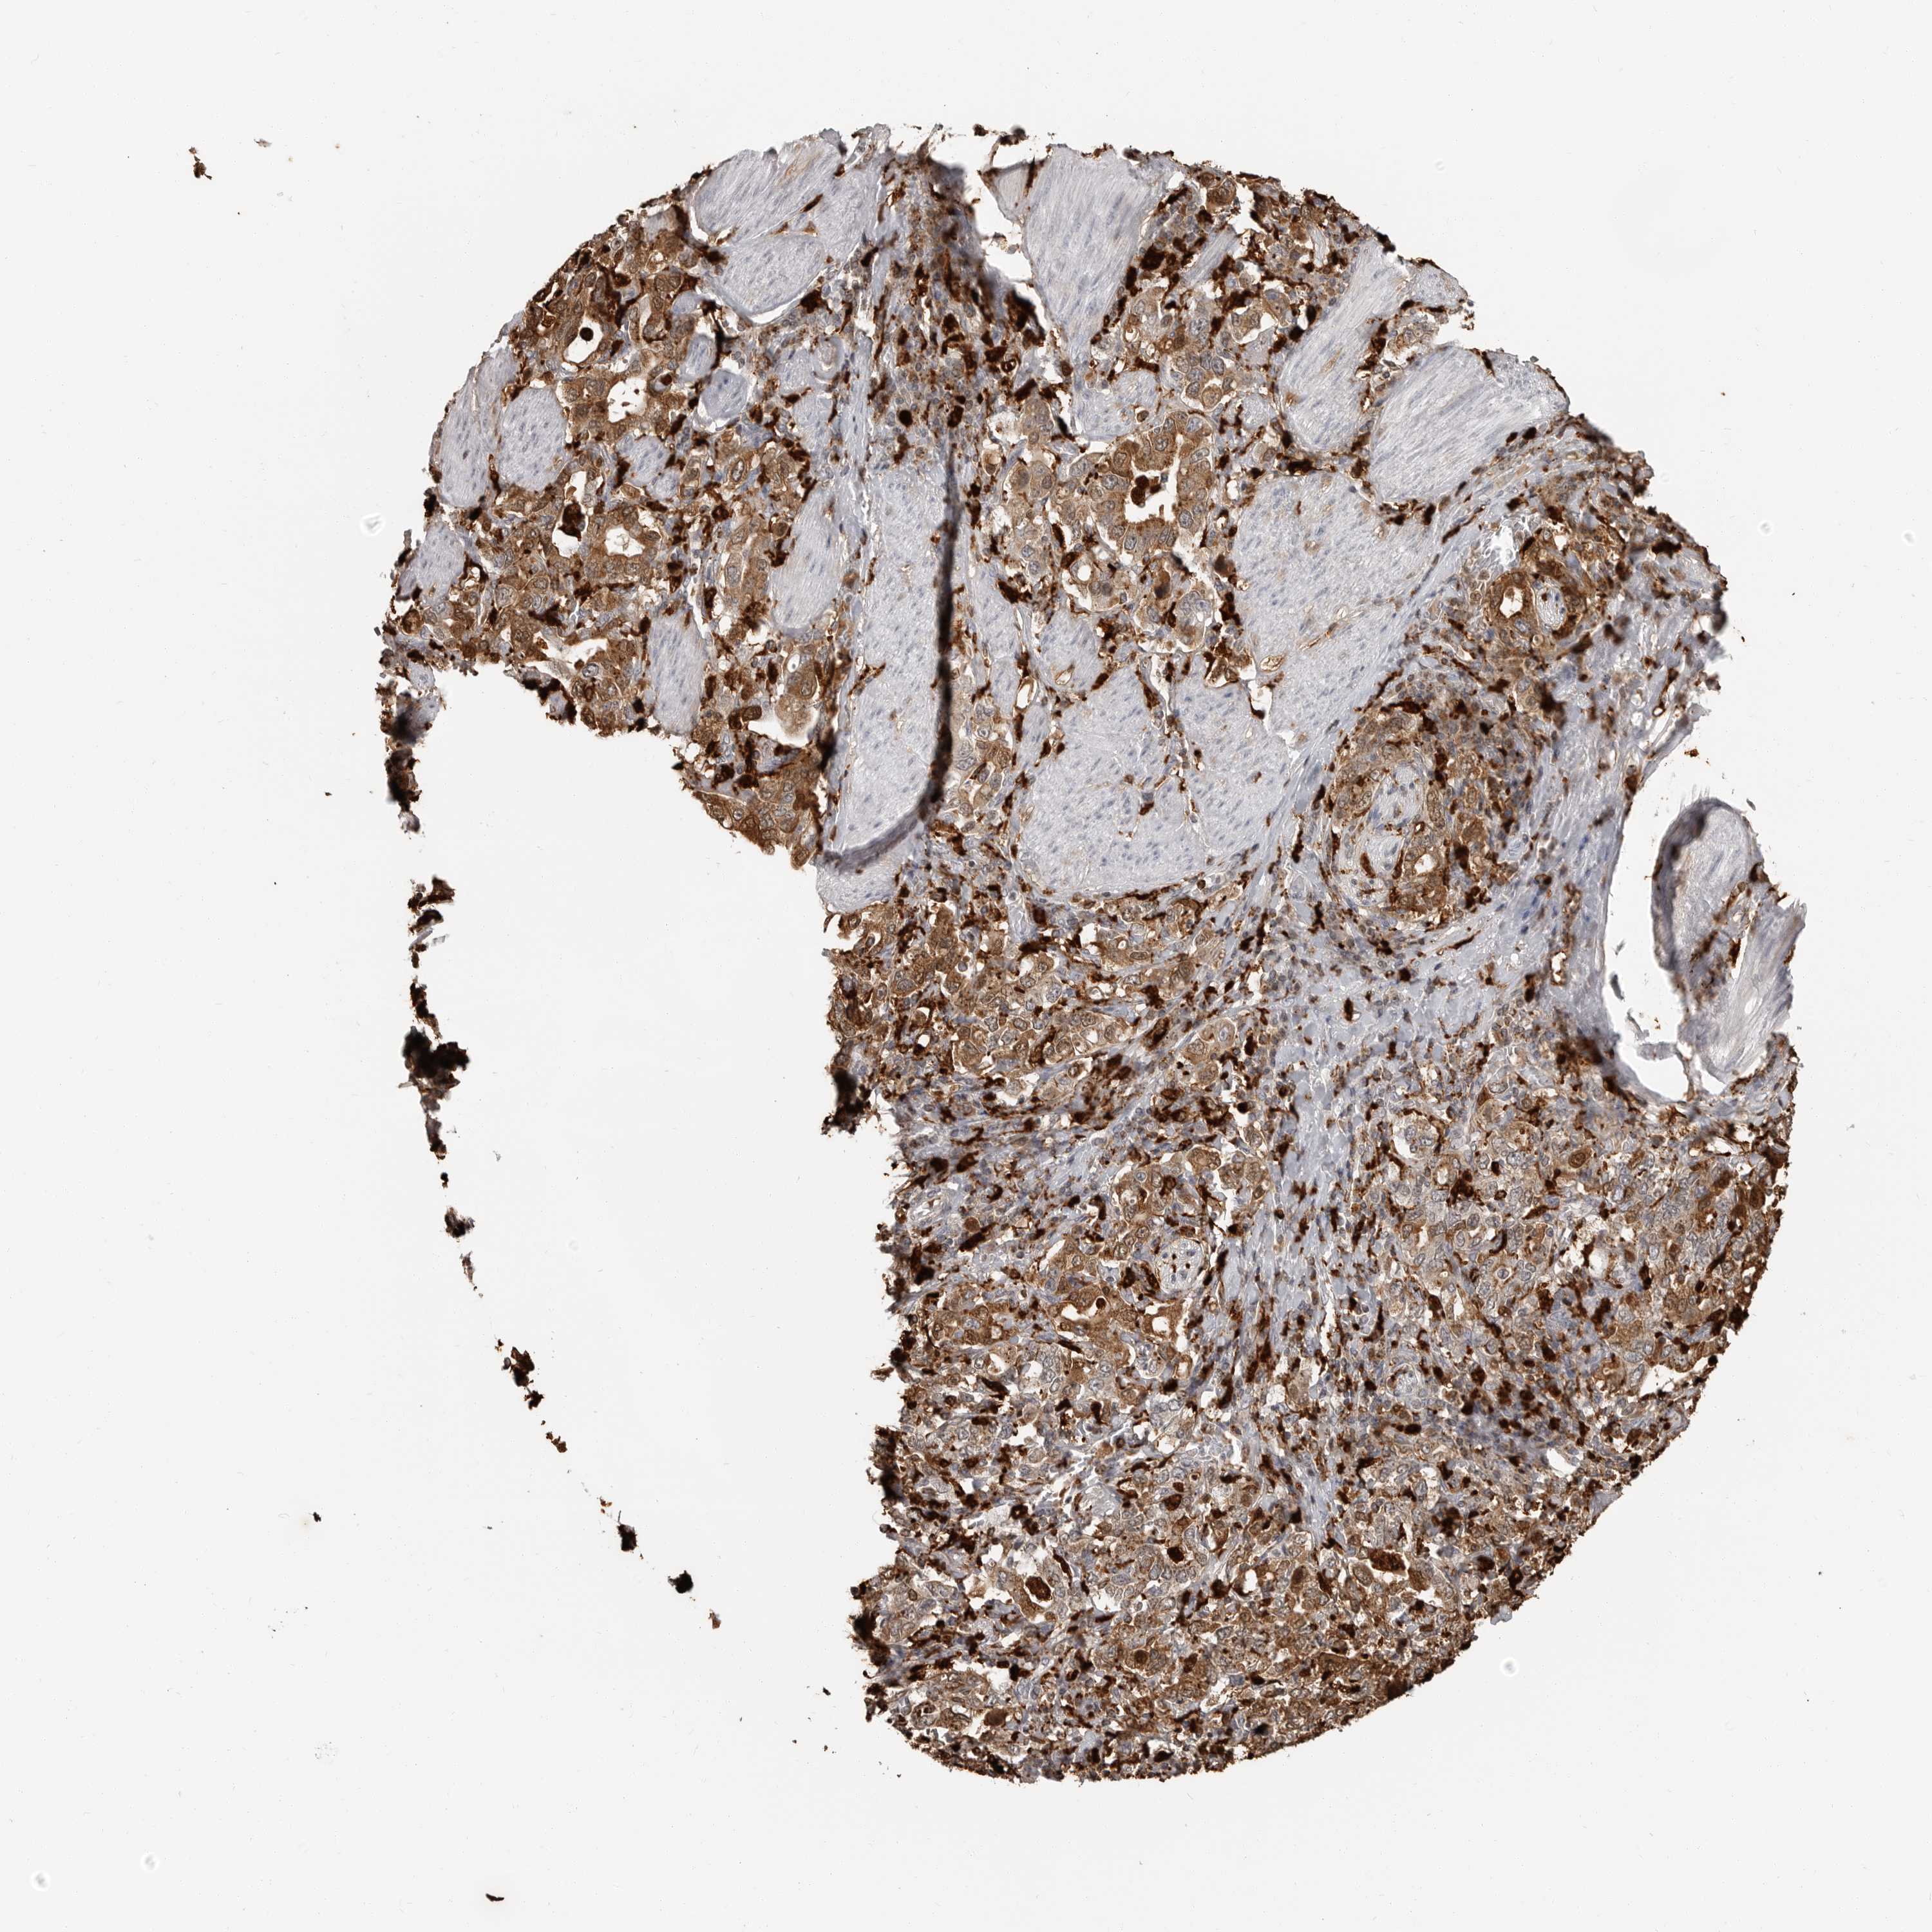

STOMACH CANCER - Protein expressioni

A mouse-over function shows sample information and annotation data. Click on an image to view it in a full screen mode. Samples can be filtered based on level of antibody staining by selecting one or several of the following categories: high, medium, low and not detected. The assay and annotation is described here.

Note that samples used for immunohistochemistry by the Human Protein Atlas do not correspond to samples in the TCGA dataset.

Antibody stainingi

Antibody staining in the annotated cell types in the current human tissue is reported as not detected, low, medium, or high, based on conventional immunohistochemistry profiling in selected tissues. This score is based on the combination of the staining intensity and fraction of stained cells.

Each image is clickable and will lead to virtual microscopy that enables deeper exploration of all samples and also displays staining intensity scores, fraction scores and subcellular localization as well as patient and tissue information for each sample.

Antibody HPA026650

Staining

High

Medium

Low

Not detected

Intensity

Strong

Moderate

Weak

Negative

Quantity

>75%

75%-25%

<25%

None

Location

Nuclear

Cytoplasmic/membranous

Cytoplasmic/membranous,nuclear

Adenocarcinoma, NOS